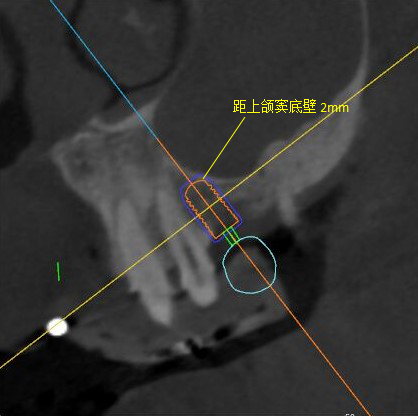

根據(jù)患者CT顯示,使用種植導(dǎo)航軟件設(shè)術(shù)前手術(shù)方案??紤]到患者拒絕手術(shù)摘除上頜竇囊腫等因素,此次手術(shù)選用了Straumann骨水平4.10*8.0mm的植體,植體末端位點設(shè)計距上頜竇底壁2mm處的同時兼顧種植方向和修復(fù)間隙,來達(dá)到理想的效果。

導(dǎo)航下精細(xì)分配修復(fù)間隙,精細(xì)規(guī)劃植入方向,避開上頜竇底,精確植入

從術(shù)后CBCT顯示可以看出,手術(shù)操作中完美地避開上頜竇底,并兼顧了正確的種植方向和修復(fù)間隙